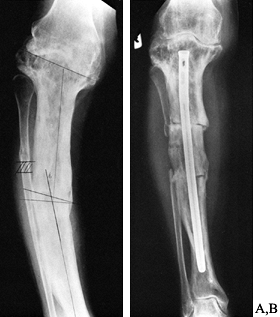

handle in patients with Paget’s disease. Intramedullary fixation is

intramedullary fixation may be required (Fig. 131.4).

![]() |

Figure 131.4. Corrective osteotomy with intramedullary fixation. A: Preoperative. B: Postoperative.